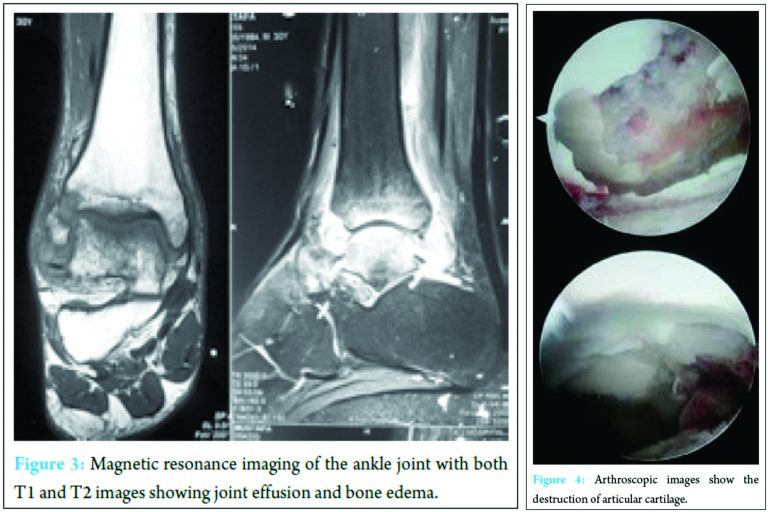

We suspected osteochondral injury of the talus and advised magnetic resonance imaging (MRI) and it showed lesions over the tibiotalar joint with joint effusion and cartilage destruction of the ankle joint (Fig. 3). On admission, laboratory findings included a white blood cell count with normal values. The erythrocyte sedimentation rate was 30 mm/h and C-reactive protein was slightly elevated. Rest all laboratory investigations were normal. In view of long-standing symptoms and MRI findings, inflammatory/pyogenic arthritis or neoplasm like osteoid osteoma of talus was suspected. With the patient in a supine position, under spinal anesthesia, the tibiotalar joint was visualized with an arthroscope after placing two standard portals. Arthroscopy was preferred because it is minimal invasive and was ideal to get tissue of interest for further investigation. Whole articular cartilage has already destroyed with lesion in the distal tibia and talus (Fig. 4).

Adequate debridement of the denuded cartilage and loose bodies with synovial tissue was done. In addition, microfracture of the exposed bone was done, and the specimen was sent to histopathological analysis and polymerase chain reaction (PCR)-GeneXpert studies. The patient was advised for nonweight bearing and ankle joint mobilization. Prophylactic antibiotic treatment was given postoperatively for 24 h. The GeneXpert for specimen showed Mycobacterium TB, without resistance for rifampicin (Fig. 5).